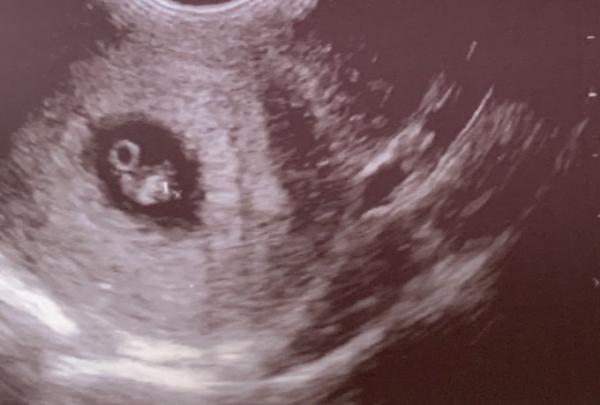

soooo bin zurück. Alles sieht gut aus Obwohl mein Eisprung später war und ich normalerweise bei 6+5 Ssw sein muss, sagte mein FA, dass ich in der 8. Ssw bin (7+1) Mein Krümel ist 1,08 cm groß und das Herz schlägt kräftig ET: 18.04.21 Den Mutterpass habe ich auch schon bekommen + ein Foto

Bild zu Huhuuu auch zurück vom FA - Forum für April - Mamis